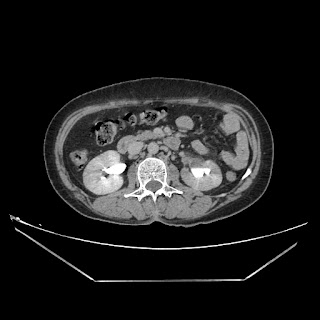

Urography images

A 50 years old woman with suffering from left sided PUJ obstruction